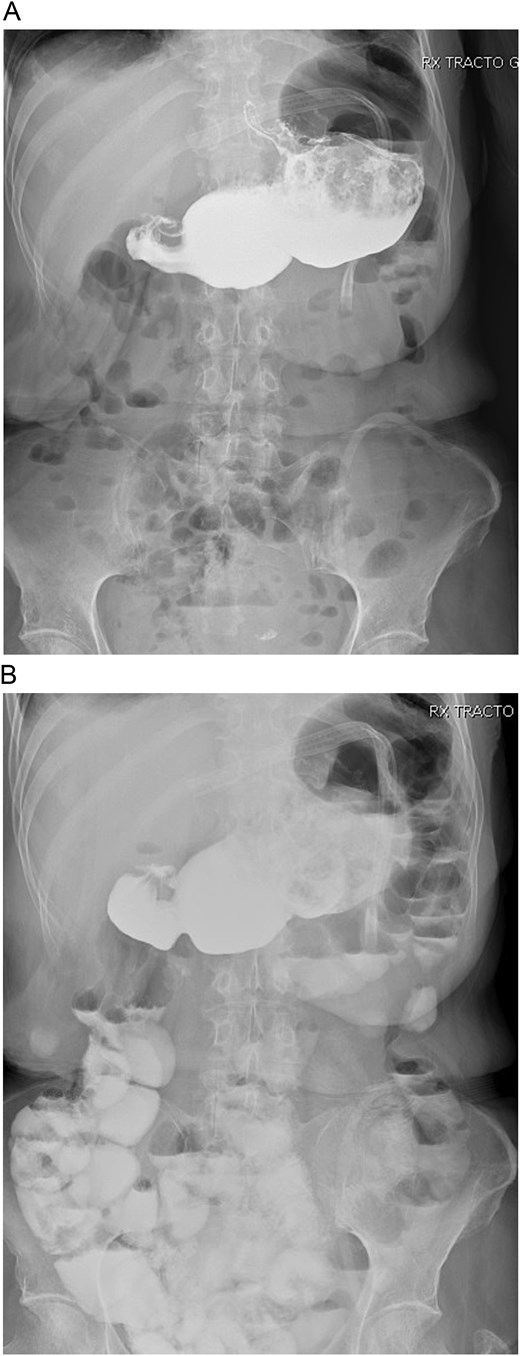

On admission, she was skinny and had bilateral edema in her extremities. Laboratory analyses showed prolonged TP and TTP (20.1 and 57.6 s), anemia (Hb: 7 mg/dl), elevated AST, ALT, GGT, and hypoproteinemia (total proteins: 3 g/dl; albumin: 1.7 g/dl). She was admitted and an endoscopy showed erythematous gastritis in an otherwise standard gastric pouch. The alimentary limb measured 80 cm and appeared normal. An abdominal computed tomography was also done, yet no masses or lymph nodes were found afterward. A bowel transit time test was also performed, which revealed that the contrast reached the anus in <30 minutes (Fig. 1A and B). A quantitative fecal fat test also revealed 9 g/24 h. With these findings, severe malnutrition due to malabsorption after an RYGB was diagnosed.

A: Bowel transit time, the complete alimentary limb and the jejunojejunal anastomosis are seen. B: Bowel transit time, in 30 minutes, it reaches the colon and anus.